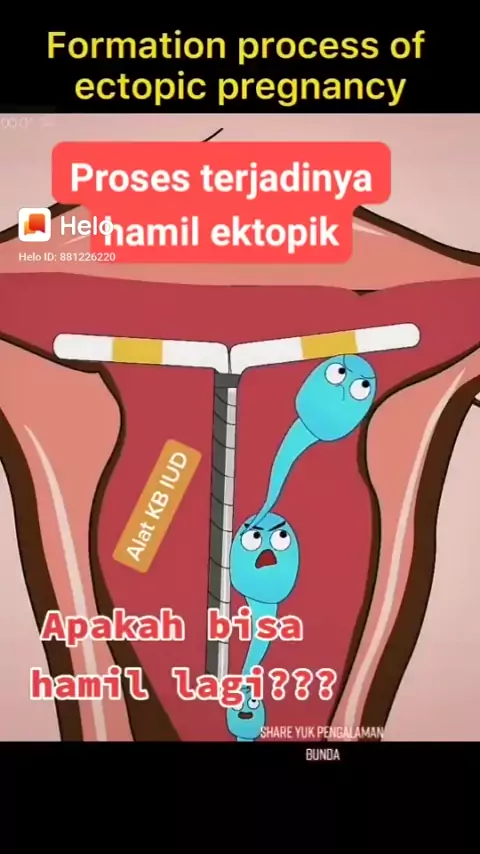

Simak ya bunda, konsul seputar kehamilan bisa lgsg klik bio diatas#melahirkan #ovulasi #promilcepathamil #pejuanggarisdua #dongggggggg #edukasikesehatan

Ada yang mau sya bantu untuk promilnya?#programhamilcepat #PejuangGarisDua #anaklucudanpintar #semogabermanfaat #Promil #konsultasipromil